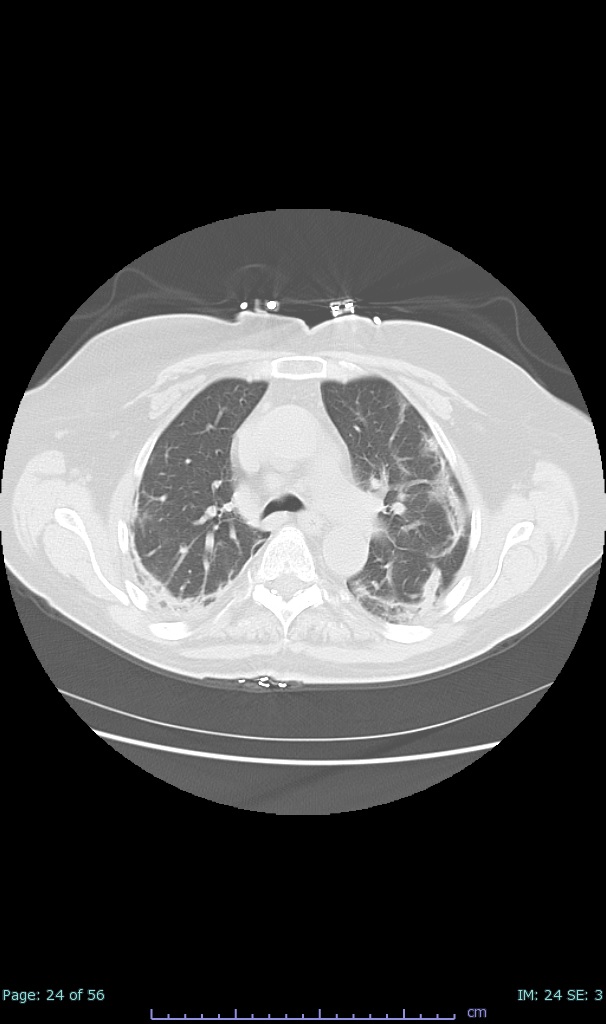

- 100% subpleural involvement, 33% + centrolobular involvement

- 40% even apical/basilar, 27% basilar dom, 5% mid dom. 1/17

- 66% had some + CXR finding I could correlate to a CT finding